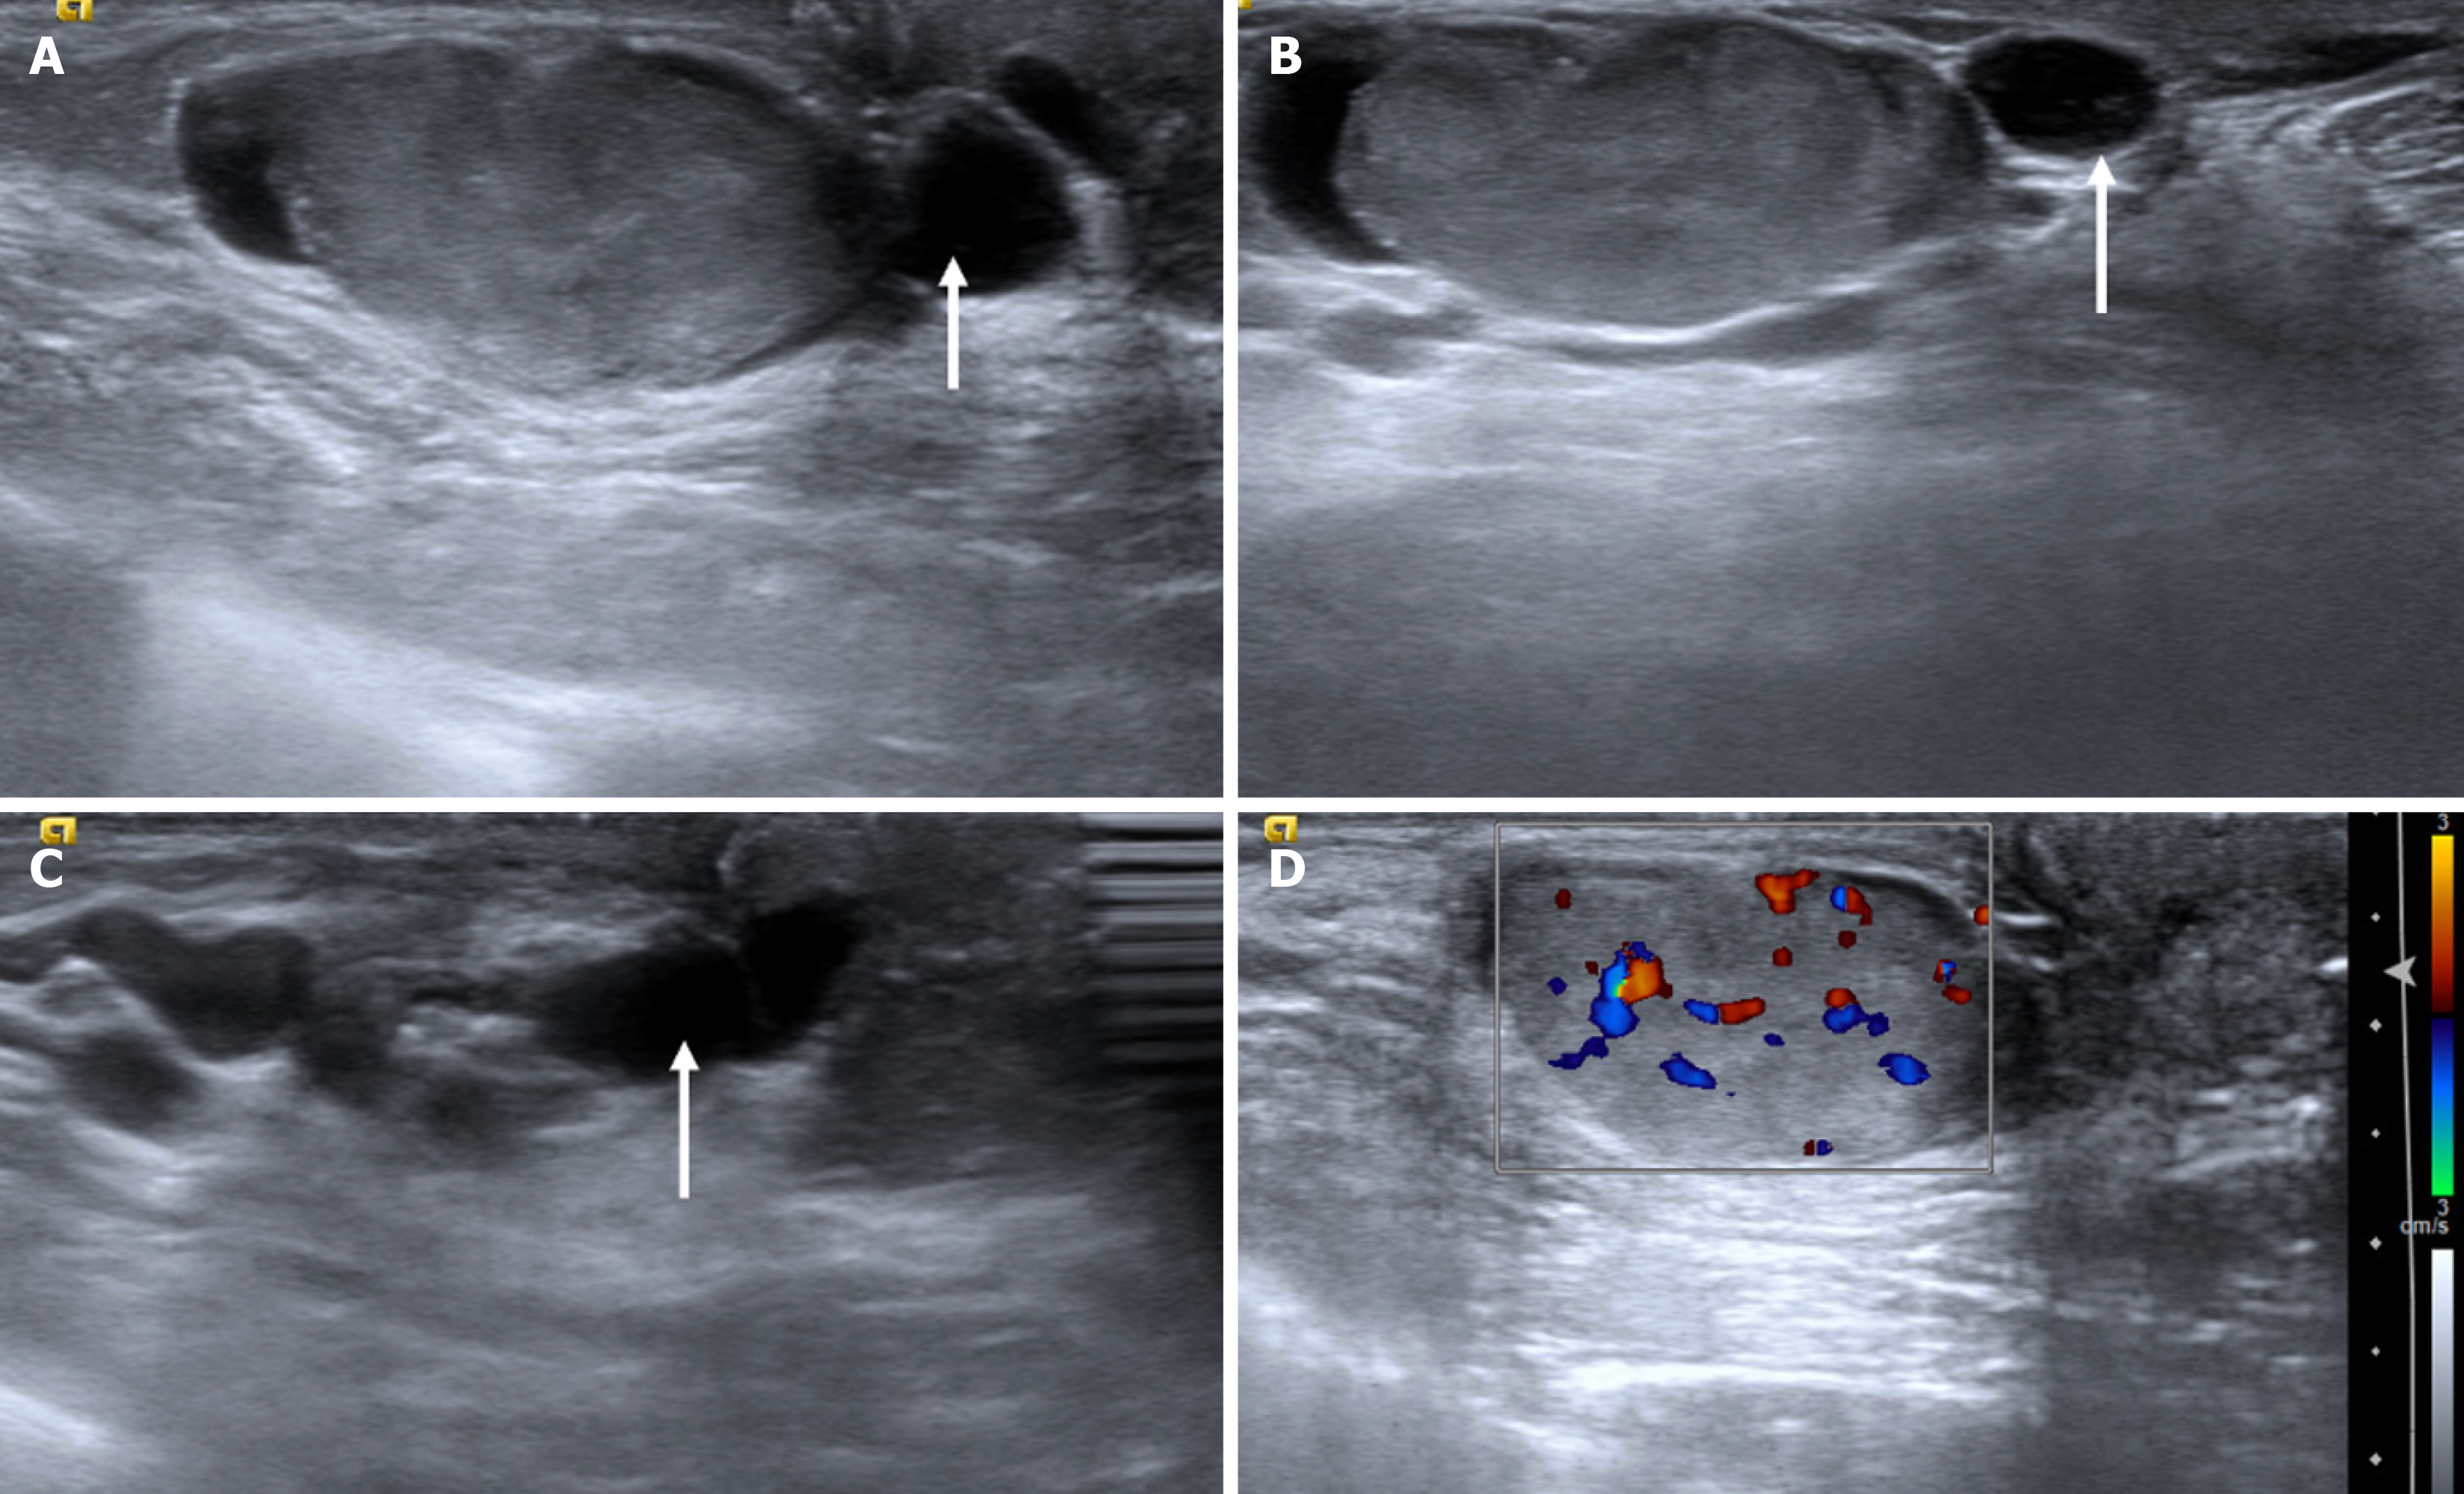

Figure 3

Pseudogynecomastia: Mediolateral oblique mammography view of a 17-year-old obese male showing a diffuse bilateral increase in fat density.

Figure 9 Mastitis with abscess in a 61-year-old diabetic male with a tender enlarged breast.

A: Ultrasound; B and C: Color Doppler images showing an irregular cystic collection with internal debris and peripheral vascularity. The surrounding fat appeared echogenic, suggesting inflammatory changes.

Figure 10  Infective collection from a 23-year-old male with a history of high-grade fever after trauma to the left breast.

A: Mediolateral oblique; B: Craniocaudal mammography views showing no obvious abnormality; C: Ultrasound; D: Color Doppler images revealing a well-defined anechoic collection with peripheral internal vascularity.